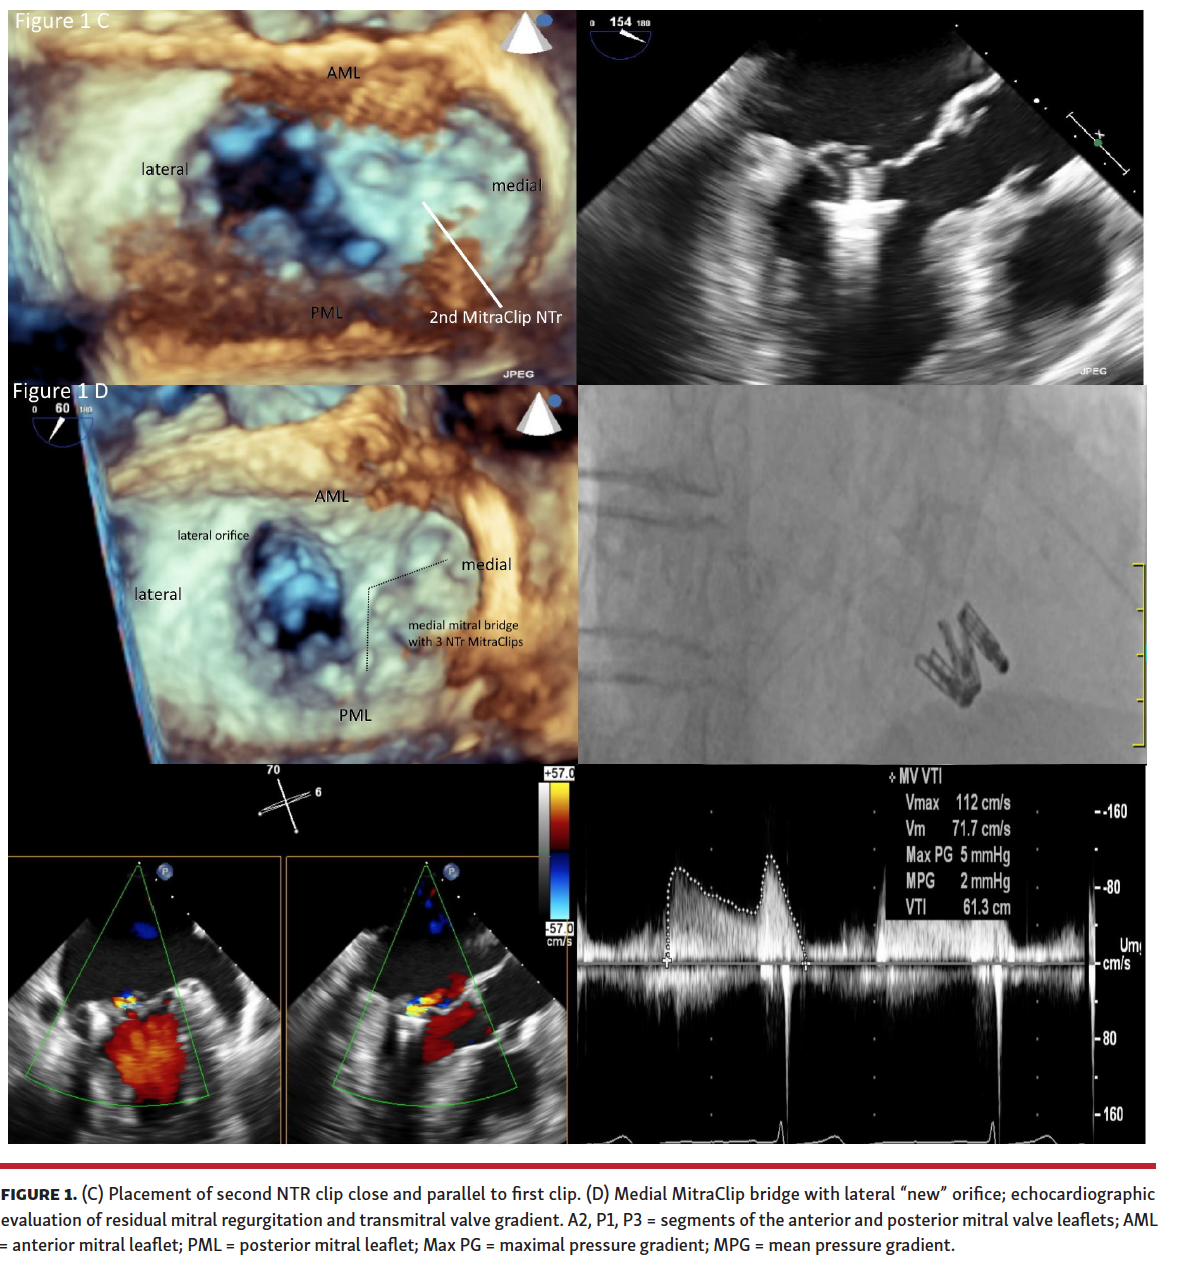

Treating Mitral Valve Prolapse in Barlow’s Disease by Creation of a Barlow Type Mitral Valve According to the cleveland clinic, barlow’s mitral valve disease is a degenerative mitral valve. What is barlow’s mitral valve disease? Degenerative mitral valve disease causing mitral valve prolapse is the most common cause of primary mitral regurgitation,. Mitral valve prolapse is a condition where the one or two of the leaflets of the mitral valve become floppy and instead of. Barlow Type Mitral Valve.

Treating Mitral Valve Prolapse in Barlow’s Disease by Creation of a Barlow Type Mitral Valve Mitral valve prolapse is a condition where the one or two of the leaflets of the mitral valve become floppy and instead of closing properly, they billow or bulge into the top chamber of. Barlow’s valve is a clinically important form of degenerative mitral valve (mv) disease that is characterized by unique clinical,. What is barlow’s mitral valve disease? Degenerative. Barlow Type Mitral Valve.